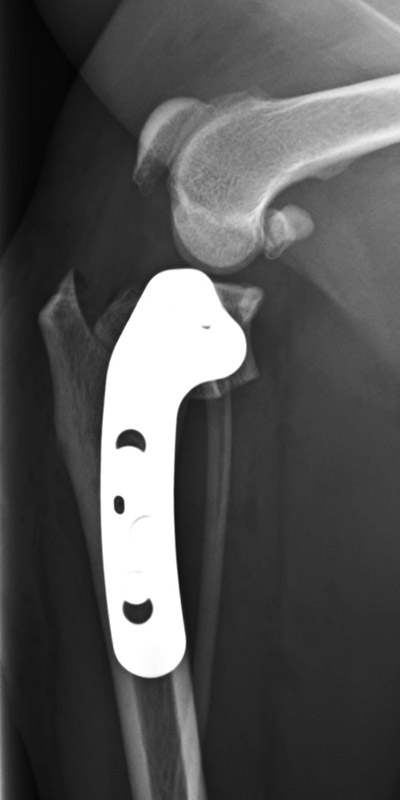

前十字靱帯断裂

柴犬(10歳)

持続する右後肢の挙上、疼痛

手術前

手術後